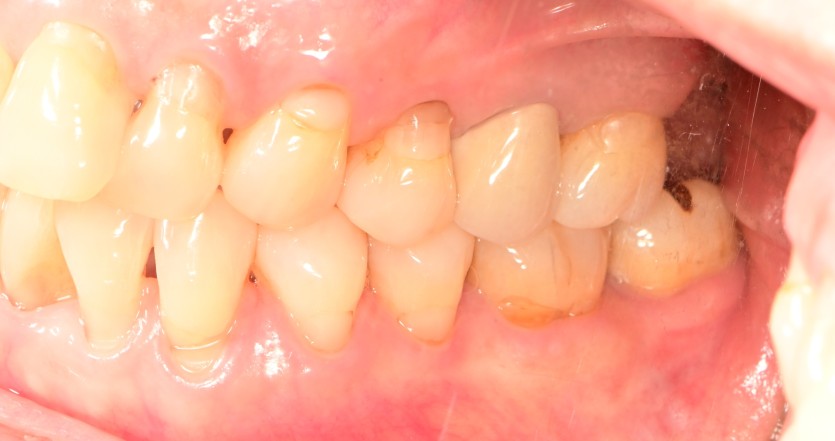

급성 턱관절염이 발생하면 발생한 쪽의 어금니가

물리지 않을 수 있습니다.

또한 턱이 한쪽으로 돌아가게 됩니다.